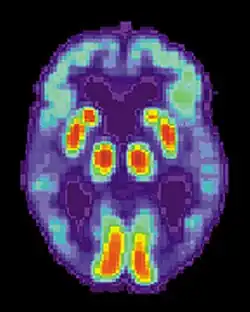

Cocaine

It is evident that long-term cocaine abuse alters brain structures. Research has shown that the brain structures that are immediately affected by long-term cocaine abuse include: cerebral hypoperfusion in the frontal, periventricular and temporal-parietal.[77] These structures play a role in various memory systems. Furthermore, the drug cocaine elicits its desirable effects by blocking the DRD1 dopamine receptors in the striatum, resulting in increased dopamine levels in the brain.[77] These receptors are important for the consolidation of procedural memory. These increased dopamine levels in the brain resultant of cocaine use is similar to the increased dopamine levels in the brain found in schizophrenics.[78] Studies have compared the common memory deficits caused by both cases to further understand the neural networks of procedural memory. To learn more about the effects of dopamine and its role in schizophrenia see: dopamine hypothesis of schizophrenia. Studies using rats have shown that when rats are administered trace amounts of cocaine, their procedural memory systems are negatively impacted. Specifically, the rats are unable to effectively consolidate motor-skill learning.[79] With cocaine abuse being associated with poor procedural learning, research has shown that abstinence from cocaine is associated with sustained improvement of motor-skill learning (Wilfred et al.).